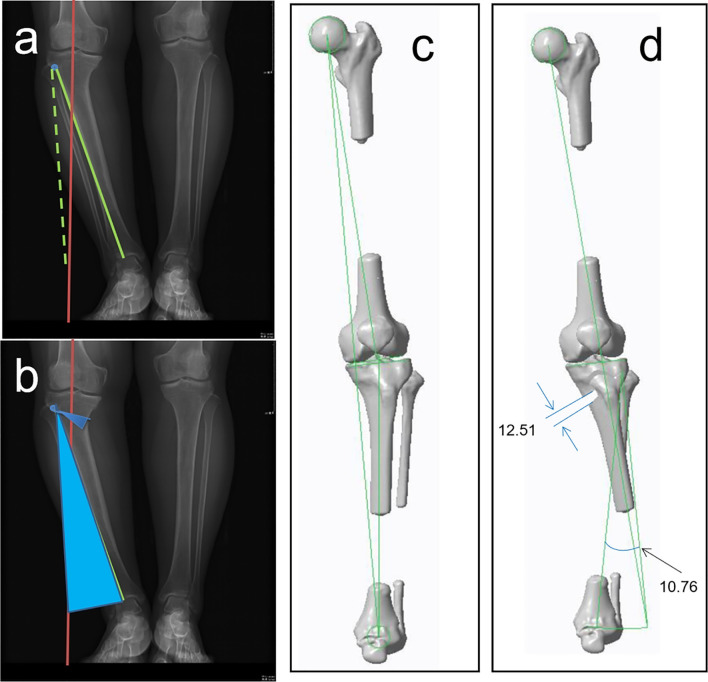

Fig. 1.

Simulated osteotomy. Lower limb 3D model was built with CT scanning data by medical image processing software and then loaded into the medical design software. The parameters of medial OWHTO were set including cutting point, lateral hinge, sawing direction, sawing depth, and correction angle. The distraction of the medial opening wedge was calculated by the "Miniaci” method according to the rotating degree of the target lower limb force line from the trigonometric perspective (a, b). The position of the lateral hinge was suggested to be about 5–10 mm from the lateral edge of the tibia plateau (c, d)